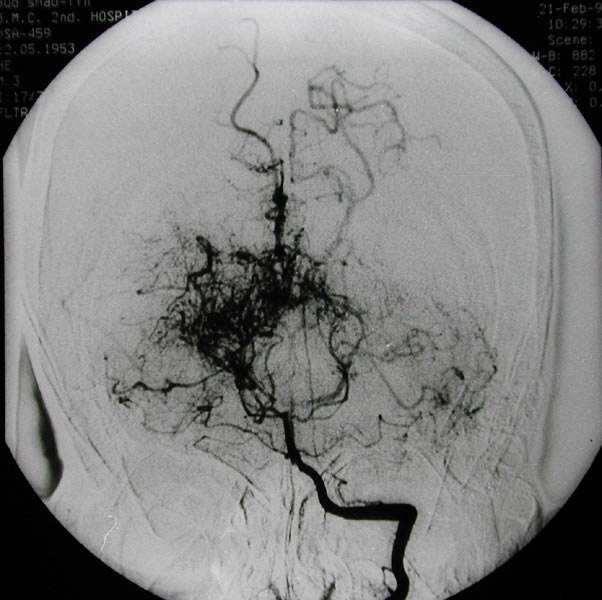

当脑血管造影图谱上浮现出那团形似烟缕的异常血管网,患者的人生轨迹便被卷入一场与时间赛跑的医疗博弈。 烟雾病 这个充满诗意的病名背后,是大脑...

烟雾病能活多久?生存率多高?Moyamoya,在日语中是烟雾的意思。 Moyamoya病也称作烟雾病是由日本的 Suzuki和 Takaku首先提出,用来描述位于Willis环和颅内近端血...

烟雾病能活多久?早期有哪些症状?烟雾病是一种进展性闭塞性脑血管病,以双侧颈内动脉末端分叉处狭窄、大脑前、中动脉异常、广泛侧支血管(烟雾血管...